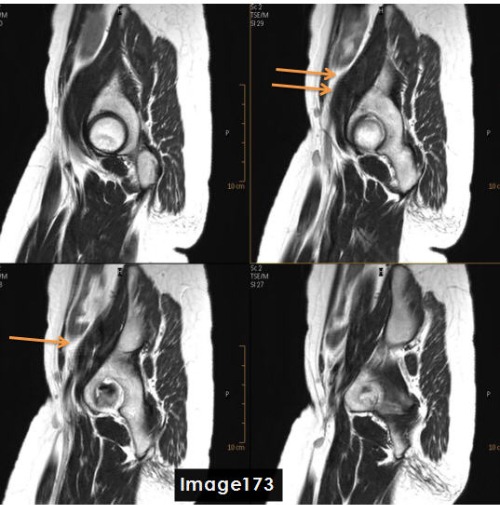

To correct for the fine line artifact shown in Image 173, which can be caused by unstable FID signals, the MRI Technologist would:

A. Increase NEX

B. Decrease NEX

C. Enable Flow Compensation

D. A or C

D. A or C (Increase NEX or Enable Flow Compensation)

The artifact identified by the orange arrows in Image 173 is a ________ artifact.

A. Chemical shift

B. FID crushing / fine line

C. Dielectric effects

D. Wraparound (aliasing)